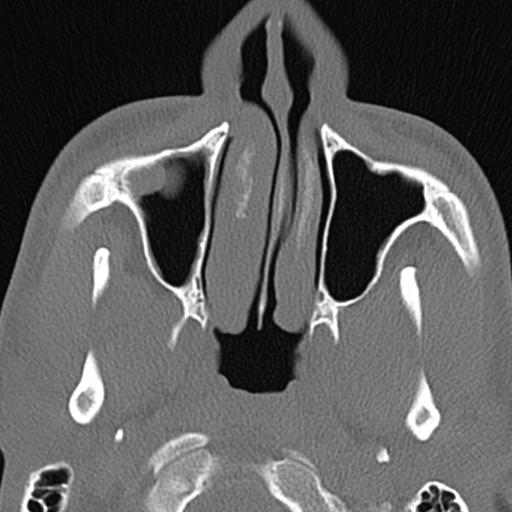

The images produced of these slices appear as if you were looking at my straight in the face and then I tilted by head back 90 deg. so that you were looking through my chin toward the top of my forehead. Hence the left side of the image is actually on my right and vice versa.

Another set of images captured vertical slices starting at the tip of my nose and proceeding back into my skull:

The prime targets of all this imaging were my septum, which divides the nasal passages leading back from each nostril, and the turbinates, which are fleshy structures capable of expanding and contracting to divert the airflow around them. My doctor already knew the septum was deviated and that inflammation of the turbinates was the cause my chronic congestion. The CT scan confirmed that, specified how, and also revealed a third problem: disease of my right maxillary sinus.

All three issues are visible in the following high-contrast image:

Here is roughly the same slice at a different contrast in which bone and soft tissue are more distinguishable: